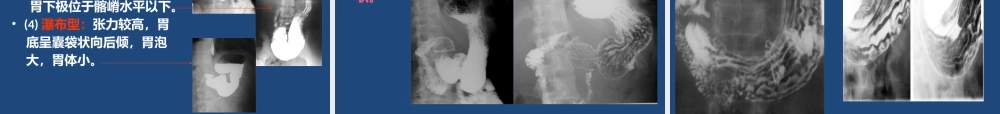

上消化道造影检查胃肠钡餐检查显示胃肠道的大体解剖形态有其优势,并可进行动态和功能观察,和内镜检查有很好的互补作用。高质量的上消化道钡剂检查和内镜相比,两者诊断的正确性非常接近。上消化道造影适应症•1、先天性食管异常•2、食管异物•3、吞咽困难或胸骨后不适感•4、怀疑消化道肿瘤或确定消化道肿瘤部位、大小、形态和范围。•5、门脉系统疾病或结缔组织疾病,观察有无食管静脉曲张或食管功能性改变。•6、了解有无纵膈肿瘤、心血管疾病、肺及胸膜病变等疾病对食管、胃或十二指肠外压性和牵拉性改变•7、上消化道肿瘤术后上消化道造影检查禁忌症•1、上消化道出血活动期•2、腐蚀性食管炎急性期•3、肠穿孔、低位小肠梗阻。•4、一般情况极差,难以耐受检查者。硫酸钡造影的观察内容粘膜皱壁:走行方向、光滑度、连续性、宽度管腔:大小、轮廓、钡剂通畅度管壁:柔软性、收缩性消化道的位置和活动度:分布位置、活动度硫酸钡造影前的病员准备检查日晨禁饮、禁食如有幽门梗阻者应抽尽潴留液钡灌肠检查,如需显示消化道粘膜,应吃少渣饮食1-2天,检查前晚口服泻剂、清除粪便,检查当日禁饮、禁食。必须严格执行!碘剂钡剂的浓度180~250%W/V钡剂的量200ml胃肠道双对比检查用钡病人在检查时先给予适量产气粉,使胃腔有适当的充胀,然后给予吞服钡剂并在透视下观察,并按一定的顺序进行观察和摄片。常用的上消化道钡剂检查摄片体位食管双对比相(站立左右前斜位)食管充盈相或粘膜相(站立左右前斜位)胃双对比相(仰卧左前斜位)胃双对比相(仰卧右前斜位)胃体、胃窦充盈相(俯卧位)胃底、贲门双对比相(左前斜位)胃底、贲门双对比相(右前斜位)十二指肠球和圈充盈相十二指肠球和圈双对比相十二指肠球和胃窦部加压相全胃充盈相(半卧位、立位)不同角度的全胃充盈相或作加压影像观察与分析正常影像学表现基本病变表现上消化道正常影像学表现.食管.胃.十二指肠食管•分段颈段胸段腹段•二个生理性狭窄入口处膈食管裂孔处或说3个加一个平主支气管分叉处•三个生理性压迹主动脉弓压迹左主支气管压迹左心房压迹消化道正常影像表现(钡剂造影)•食道钡剂造影的正常表现:表现为一边缘光滑的管状,数条纤细纵行而平行的粘膜皱襞,右前斜位:在食管前缘可见自上而下的三个生理压迹,主动脉弓、左主支气管、左心房压迹。食管正常钡餐造影检查表现•食管充盈像•1、轮廓光整,宽度可达2-3CM•2、管...